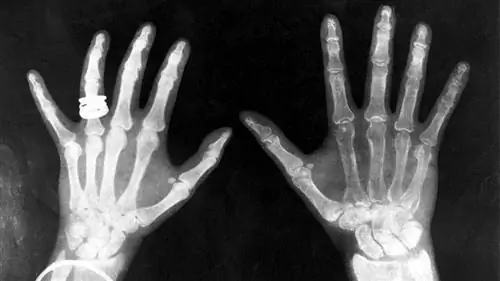

рентгеновские снимки короля Георга и королевы Марии

Рентген помещал между трубкой и экраном разные предметы, а экран все равно светился. Наконец, он поднес руку к трубке и увидел силуэт своих костей, спроецированный на флуоресцентный экран. Сразу после открытия самих рентгеновских лучей он обнаружил их наиболее полезное применение.

Замечательное открытие Рентгена ускорило одно из самых важных медицинских достижений в истории человечества. Рентгеновская технология позволяет врачам видеть прямо сквозь ткани человека, чтобы с необычайной легкостью исследовать сломанные кости, полости и проглоченные предметы. Модифицированные рентгеновские процедуры можно использовать для исследования мягких тканей, таких как легкие, кровеносные сосуды или кишечник.

Мягкие ткани вашего тела состоят из более мелких атомов и поэтому плохо поглощают рентгеновские фотоны. Атомы кальция, из которых состоят ваши кости, намного крупнее, поэтому они лучшепоглощают рентгеновские фотоны.

Как правило, врачи сохраняют пленочное изображение какнегатив То есть области, подвергающиеся большему воздействию света, кажутся темнее, а области, подвергающиеся меньшему воздействию света, кажутся светлее. Твердый материал, например кость, выглядит белым, а более мягкий материал - черным или серым. Врачи могут сфокусировать различные материалы, изменяя интенсивность рентгеновского луча.